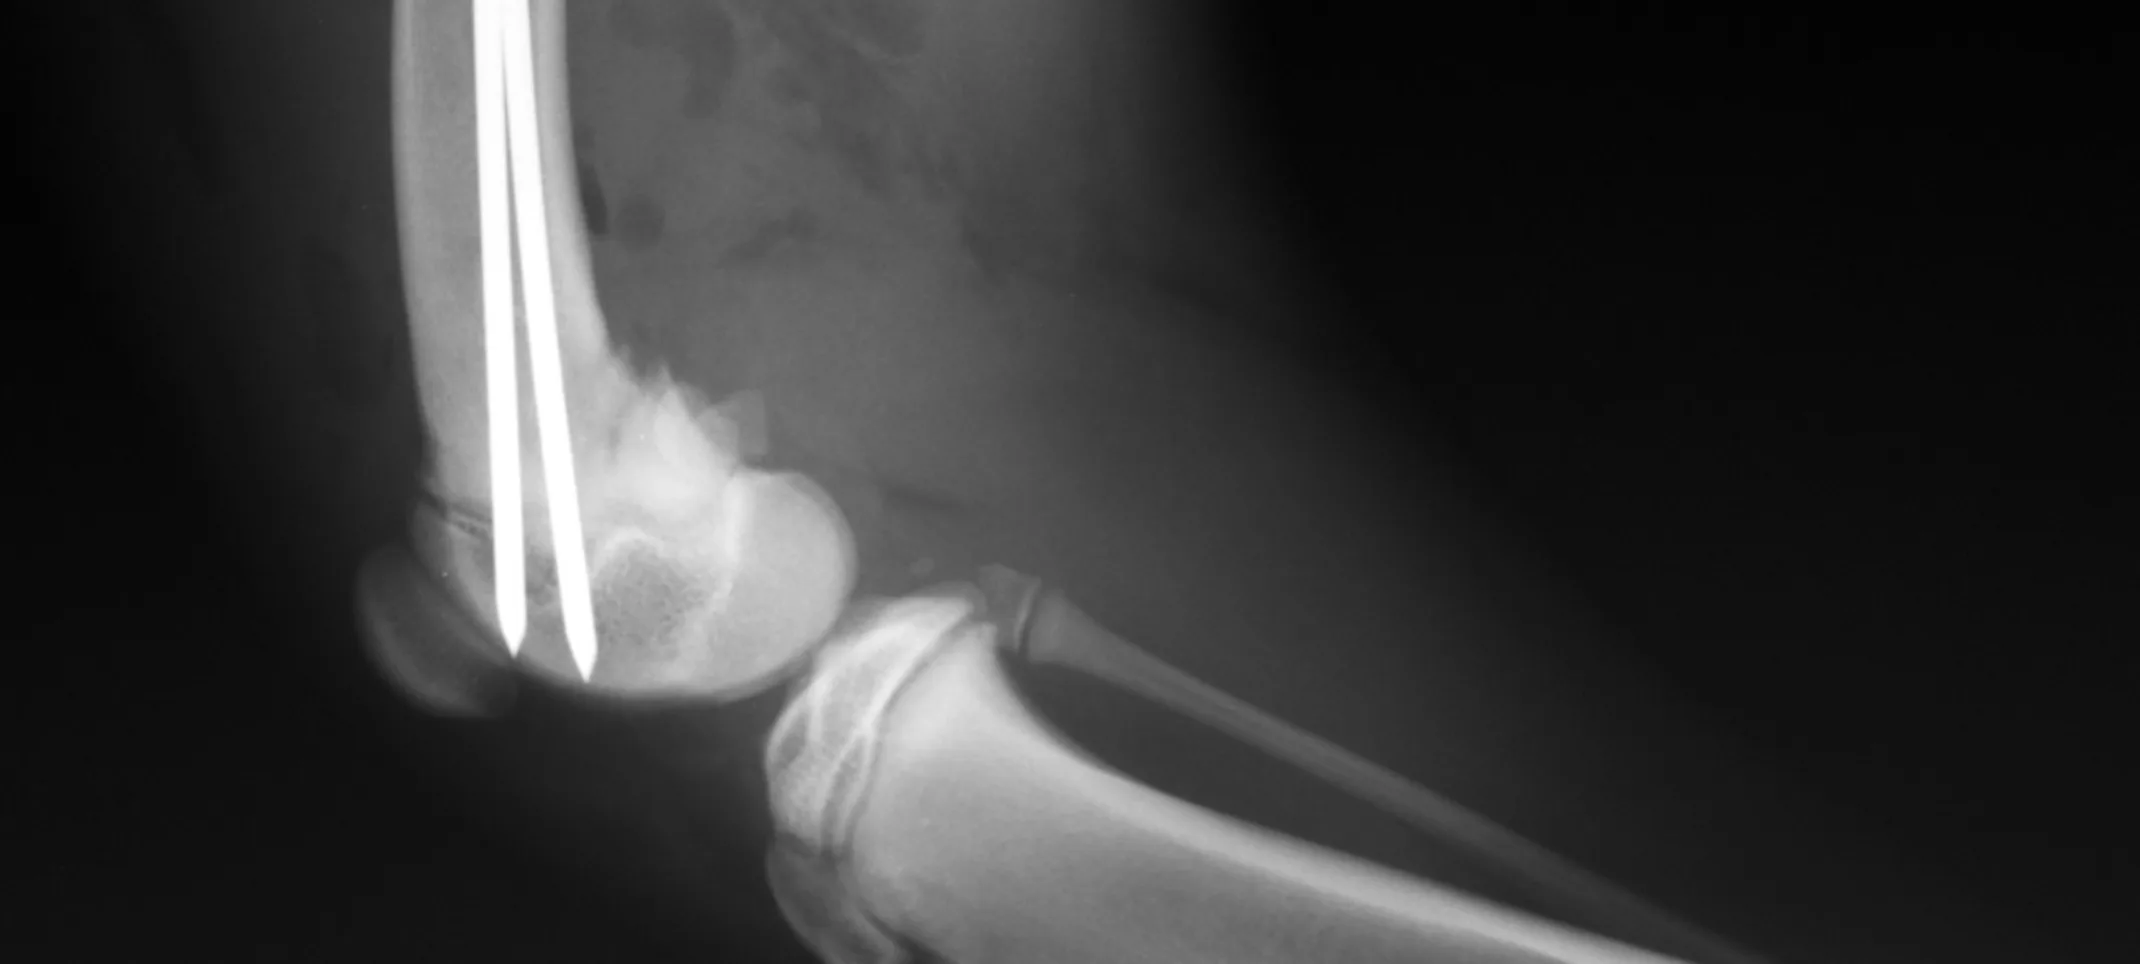

X-rays can be used to detect a variety of ailments in animals including arthritis, tumors, bladder and kidney stones, and lung abnormalities such as pneumonia. They are also used to evaluate bone damage, the gastrointestinal tract, respiratory tract, genitourinary system, organ integrity, and even identify foreign objects that may have been ingested. Dental radiographs help distinguish healthy teeth from those that may need to be extracted, and identify any abnormalities beneath the gums including root damage, tumors, and abscesses. In some cases, we may need to sedate your pet or use short-acting general anesthesia.